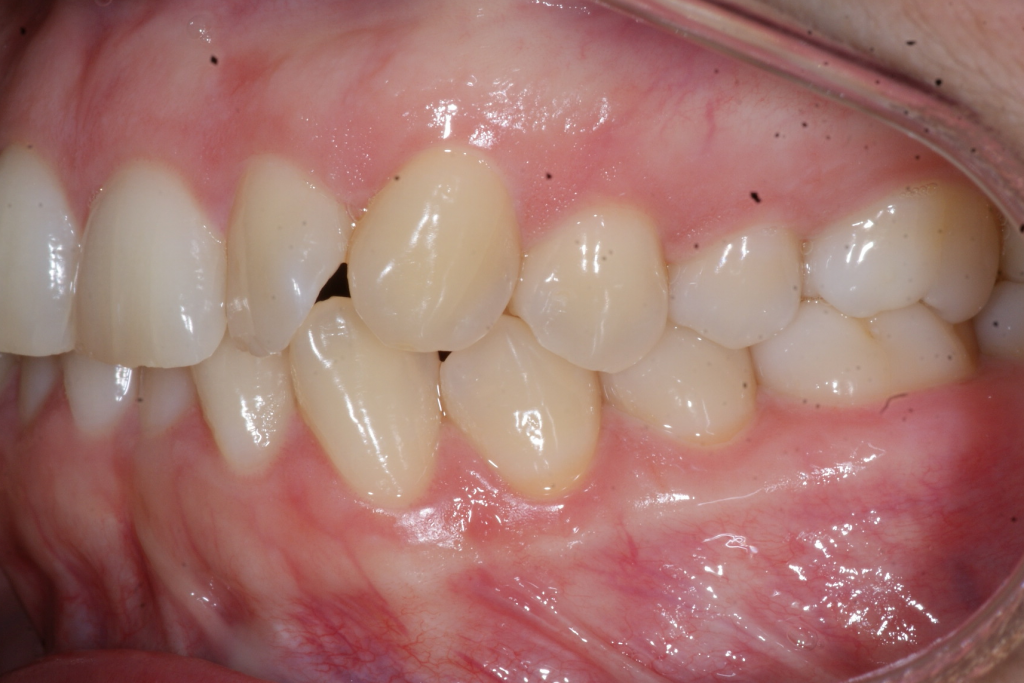

Correction d’une malocclusion de type Classe I, surplombs inadéquats et chevauchement modéré aux 2 arcades.  57 coquilles furent nécessaires pour améliorer ce sourire.  Traitement chez une adulte, réalisé en 15 mois.